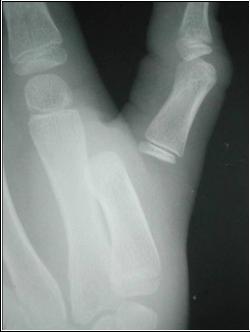

Dislocations